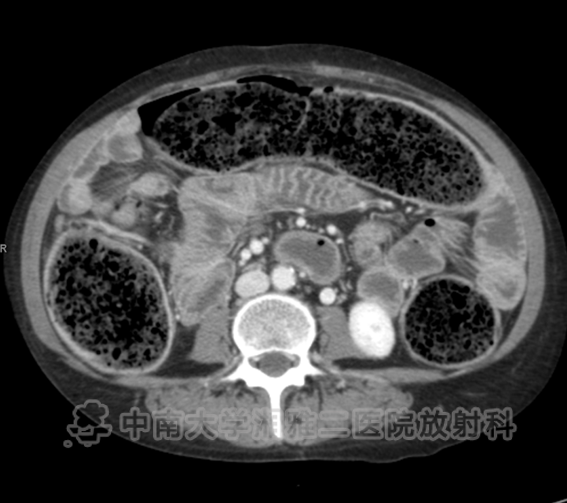

● 在结肠中有明显的粪块残留,在结肠壁(箭头)内存在气体,相关肠壁无增厚或肠系膜脂肪的滞留,与结肠囊样积气一致。

● 在空肠(箭头所示)中有一堆又细又直的褶皱。